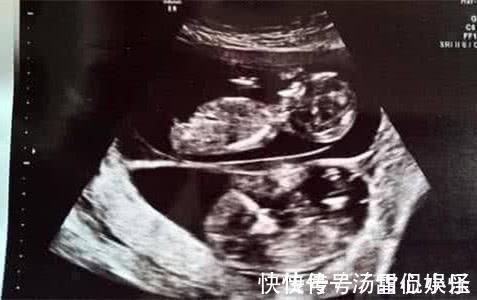

本文配图均源网络,图文无关然而孕12周,小方在丈夫的陪伴下来到医院产检时,医生竟然发现她肚子里的双胞胎竟然一个大一个小,而且与那些抢夺营养的双胞胎导致的一大一小不同,小一点的那个胎儿甚至都无法做超声波扫描。医生告诉小方夫妻,其实她肚子里的两个孩子不属于常规意义的双胞胎,而是一种特别罕见的“复孕”现象,是由两枚在不同月经周期排出的卵子先后孕育的,受精着床时间相隔3周左右。于是这两个胚胎有各自的胎盘,也有不同的预产期。小方顿时回忆起来,就在不久前,因为心疼丈夫,她主动提起同房。那次两人以为怀孕后就不需要做安全措施,于是就忽视了。医生听完,不由叹气:“简直心大!第一次来孕检我就说了孕早期不可以同房,现在出现这种情况,你知道第二个会有多危险吗?”